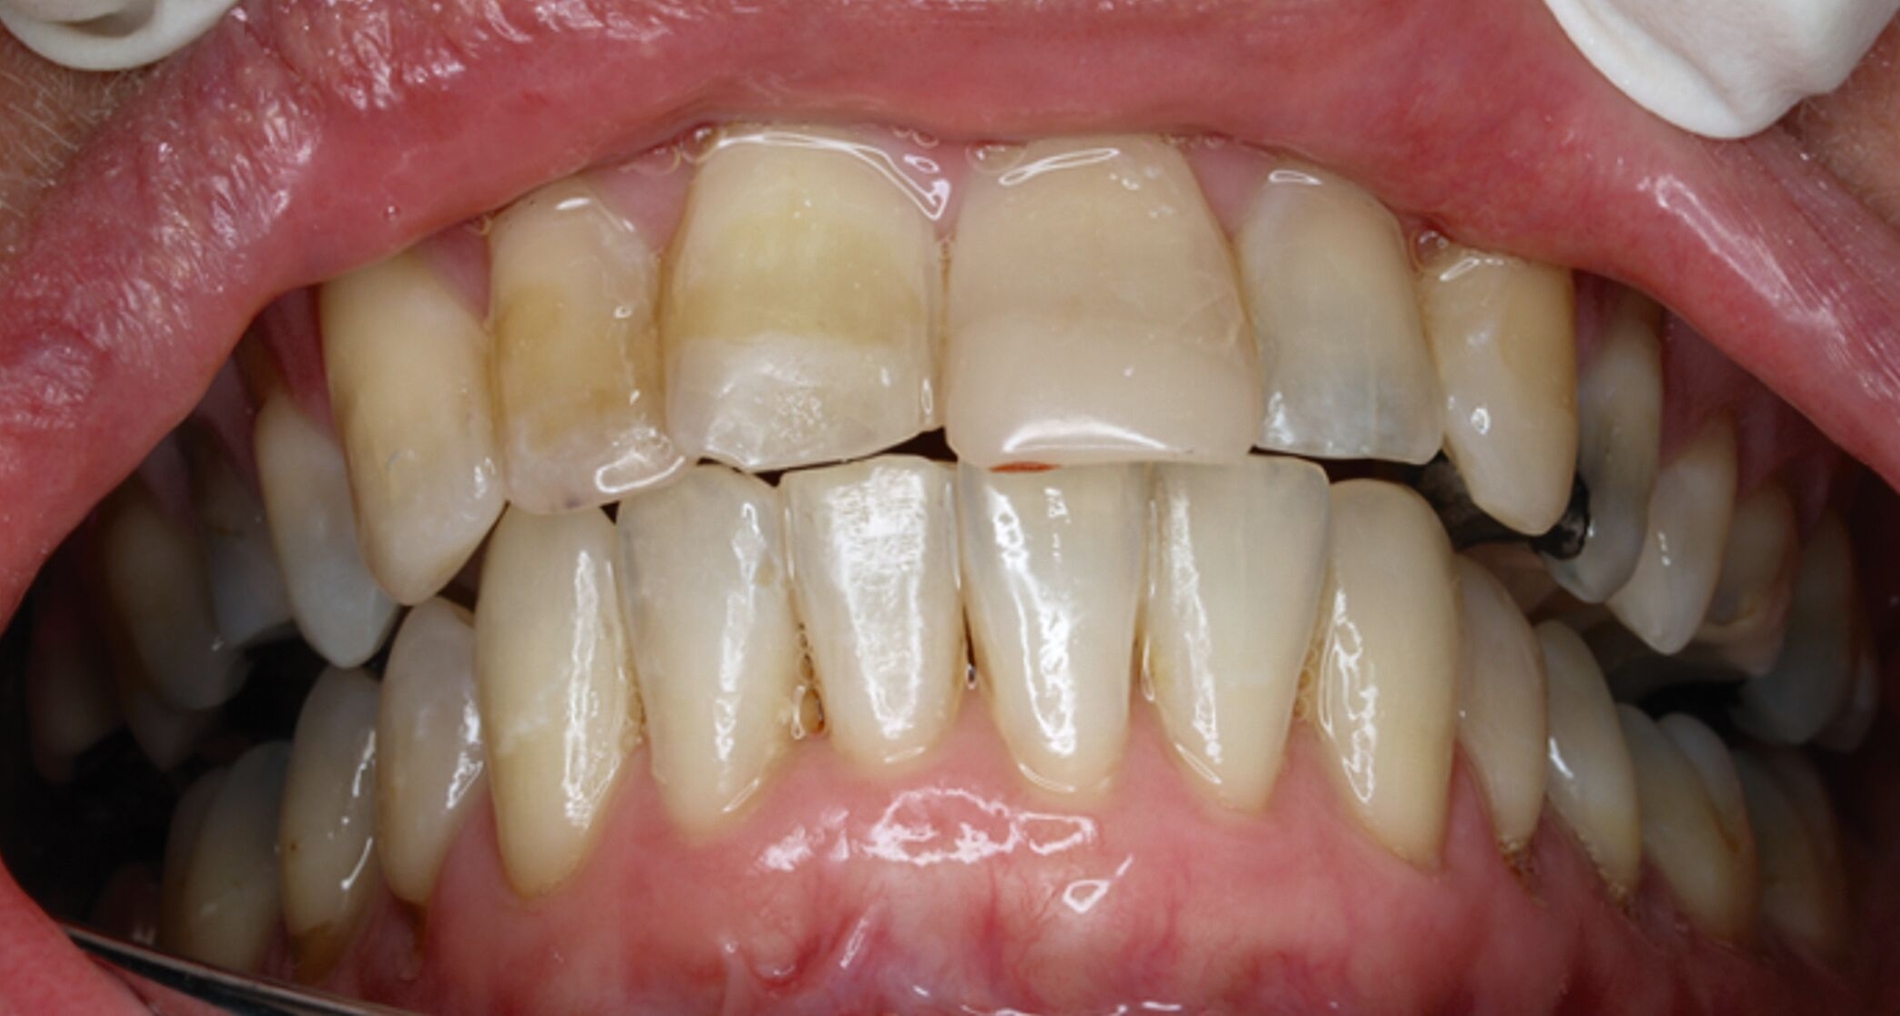

Klinisch zeigten sich diverse großflächig, mehrheitlich mit Amalgam gefüllte Seitenzähne, suffiziente endodontische Behandlungen an den Zähnen 16 und 14 sowie intakte Kronen an den Zähnen 16 und 48 (Abbildung 2). Ein Parodontaler Screening-Index (PSI) wurde erhoben (1-1-0-0-2-1), der stabile Verhältnisse nachwies. Das funktionelle CMD-Screening zeigte eine nicht-druckdolente Kaumuskulatur sowie eine uneingeschränkte Mundöffnung ohne Reiben und Knacken.

Tabelle 1 zeigt das entsprechende Befundschema mit den Taschentiefen mesial und distal, den Lockerungsgraden und den Sensibilitätsüberprüfungen mittels Kältespray (ViPr). Die Ruheschwebelage wurde mithilfe des Zielinsky-Zirkels auf 2 mm bestimmt. Die Nonokklusion im Seitenzahnbereich konnte auf circa 1,5 mm bemessen werden. Tabelle 2 spiegelt das entsprechende Okklusionsprotokoll wider. Das Okklusionsprofil wird auch in den Abbildungen 3a bis 3c deutlich.